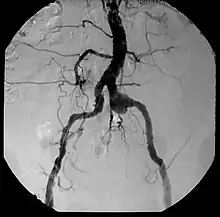

| Aneurysm, a commonly lethal complication of SA | |

Inflammatory involvement of tertiary syphilis begins at the adventitia of the aortic arch which progressively causes obliterative endarteritis of the vasa vasorum.[3] This leads to narrowing of the lumen of the vasa vasorum, causing ischemic injury of the medial aortic arch and then finally loss of elastic support and dilation of the vessel.[3] Dissection of the aortic arch is rare due to medial scarring. As a result of this advanced disease process, normal methods of angiography/angioplasty may be impossible for those with suspected coronary artery disease.